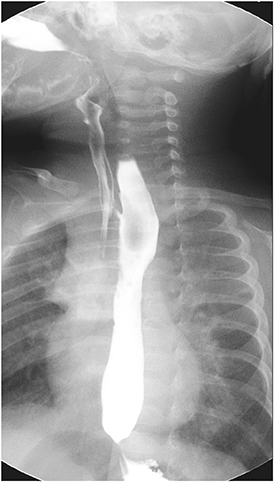

rd day of life, and an H-type TEF was found at 1 cm above the carina, at T4 level (

Fig. 2). Surgical repair was performed on the 37

Fig. 2 H-type tracheoesophageal fistula at 1 cm above the carina (white arrows).

Routine esophagogram taken on postoperative day 10 still showed an evidence of fistula (

Fig. 3). Recurrence or presence of another H-type fistula had been suspected. To confirm the diagnosis, rigid bronchoscopy was scheduled under general anesthesia on postoperative day 15. However, the bronchoscopy failed to demonstrate the opening of the fistulous tract even under positive ventilation.

Fig. 3 Another H-type fistula at T2 level.